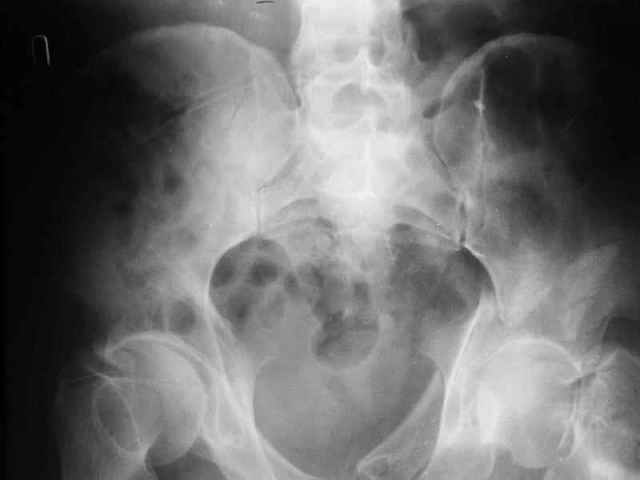

Больной 18 мая 2003 года в автоаварии получил перелом левой вертлужной впадины, вывих бедра. Госпитализирован в один из стационаров области.Вывих вправлен. В последствии бедро вывихивалось еще дважды. На консультацию был представлен снимок от 19.05.03г., больной переведен к нам 3.06.03г. Снимок при поступлении - перелом впадины, задне-верхний вывих бедра. 05.06.2003 г. выполнено открытое вправление вывиха левого бедра и остеосинтез стенки вертлужной впадины двумя винтами. Послеоперационный период без осложнений. Объем движений в левом тазобедренном суставе восстановился полностью. Выписан на амбулаторное лечение в удовлетворительном состоянии с рекомендациями 3 месяца ходить на костылях без нагрузки на оперированную конечность. На контрольных рентгенограммах левого тазобедренного сустава 13.10.2003 г. - признаки консолидации перелома; плотность, форма головки и состояние суставных поверхностей удовлетворительные. Разрешена дозированная осевая нагрузка, на конечность с использованием дополнительной опоры. 19.12.2003 г. больной обратился с жалобами на боли в левом тазобедренном суставе. На рентгенограммах левого тазобедренного сустава 19.12.2003 г., 20.02.04г. - асептичекий некроз головки бедра. 5.04.04г. - эндопротез. Сейчас ходит без трости, не хромает. Особенность эндопротезирования - при удалении винтов прослежена линия перелома заднего края впадины и предложено установить чашку несколько меньшего диаметра, чтобы она была покрыта несломанной частью.

Случай, представленный Вами, совсем не идентичен обсуждаемому. У Вашего пациента был поперечный перелом с переломом заднего края, а в обсуждаемом случае - высокий двухколонный перелом вертлужной впадины.

То есть в представленном Вами случае был перелом заднего типа, в нашем случае центрального. У Вашего больного был застарелый задний вывих, у нашего - перелом шейки. Столь раннее разрушение головки, вероятно, было во многом обусловлено тем, что не была достигнута анатомическая репозиция, головка бедра осталась смещенной кзади, что является частой ошибкой при крупных фрагментах свода.

Необходимость фиксации вертлужной впадины в нашем случае вообще под вопросом, так как конгруэнтность сохранена (вторичная конгруэнтность типична для двухколонных переломов).

Наш больной пока обследуется, сделали сегодня КТ наконец-то.